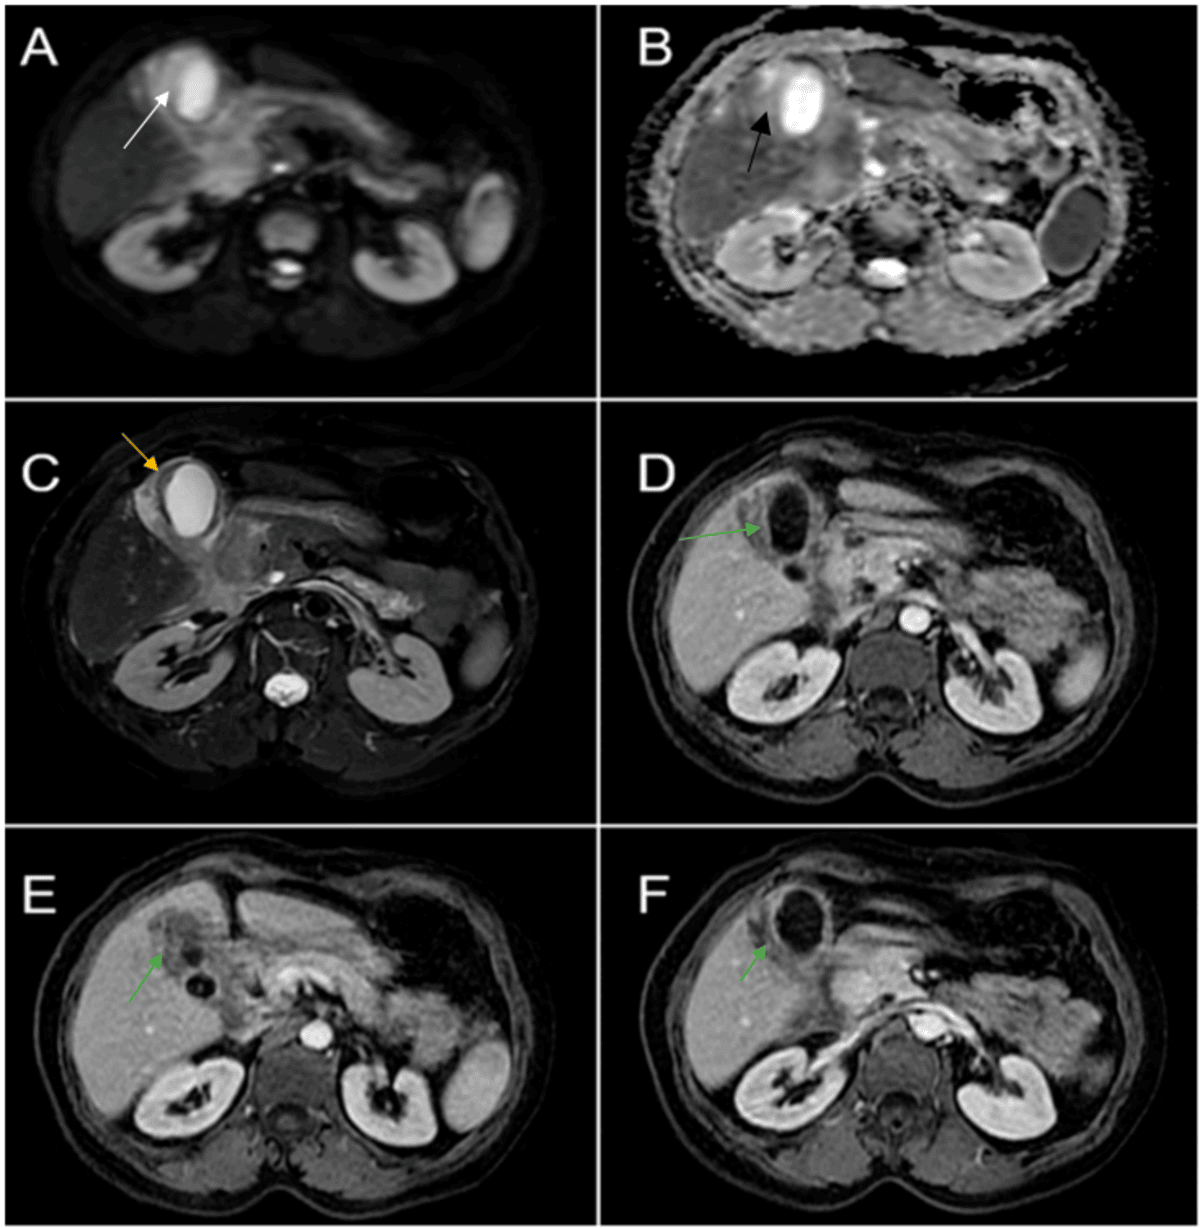

Diffusion Restriction: Describes tissues that impede water movement, often suggesting malignancy due to increased cellular density.

Malignant thickening of the gallbladder wall on MRI typically appears as diffuse, nodular thickening with disrupted mucosal lines and absence of the normal layered appearance; apparent diffusion coefficient (ADC) values can help differentiate malignant from benign causes, with malignancy showing low ADC values and early contrast enhancement15,23,24.

MRI provides clear visualisation of local and advanced invasion, especially into the liver, using hepatobiliary contrast agents and dynamic scanning, often delivering higher sensitivity than other modalities; delayed enhancement in adjacent tissues can indicate hepatic involvement18,20,25.

MRI’s superior soft tissue characterisation allows for the detection of small, early-stage gallbladder lesions that might be overlooked by ultrasound or computed tomography (CT), including small intraluminal masses or subtle wall thickening. This makes MRI especially valuable for comprehensive assessment in complex or inconclusive cases2,15,18,20.